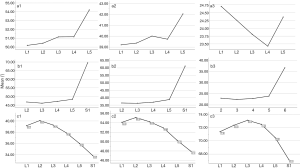

The angles of oblique fixation from posterior corner in lumbar spine in sagittal and axial planes (Figures 5-9).

a1: the angle between the line, which is from the posterior-lower corner of the upper vertebral body to front-middle 1/3 of the upper endplate, and lower endplate parallel line.

a2: the angle between the line, which is from the posterior-lower corner of the upper vertebral body to anterior-upper corner, and lower endplate parallel line.

a3: the angle between the line, which is from the posterior-lower corner of the upper vertebral body to the midpoint of the anterior border, and lower endplate parallel line.

b1: the angle between the line, which is from the posterior-upper corner of the lower vertebral body to front-middle 1/3 of the lower endplate, and upper endplate parallel line.

b2: the angle between the line, which is from the posterior-upper corner of the lower vertebral body to anterior-lower corner, and upper endplate parallel line.

b3: the angle between the line, which is from the posterior-upper corner of the lower vertebral body to the midpoint of the anterior border, and upper endplate parallel line.

c1: the angle between the projection, which is generated from the posterior corner of the upper vertebral body to contralateral front-middle 1/3 on the endplate, and the tangent line to the posterior border of the vertebral body.

c2: the angle between the projection, which is generated from the posterior corner of the upper vertebral body to contralateral anterior corner on the endplate, and the tangent line to the posterior border of the vertebral body.

c3: the angle between the projection, which is generated from the posterior corner of the upper vertebral body to the midpoint of the anterior border on the endplate, and the tangent line to the posterior border of the vertebral body.

The included angles a1, a2, a3, b1, b2, b3 and c1, c2 and c3 in the sagittal plane were significantly different (P≤0.001) (Figure 13) (a1 > a2 > a3, b1 > b2 > b3, c1 < c2 < c3). In the angles of sagittal down-path, b1, b2 and b3 change significantly and consistently, showing a trend of decreasing first and then increasing, which is the smallest at L3 (46.08±4.37°, 36.21±3.51°, 22.47±3.01°) and the largest at S1 (69.49±8.28°, 61.23±7.74°, 36.60±5.00°). In the angles of sagittal up-path, a1 and a2 change in the same way, showing an increasing trend. While a3 goes down and then goes up, which is the smallest at L4 (23.43±4.29°) and the largest at L5 (24.36±2.94°). In the angles of axial plane, c1, c2 and c3 change in the same way, showing a trend of increasing first and then decreasing. c1 and c2 are the largest at L2 (40.07±2.75°, 55.1±3.32°), and c3 is the largest at L3 (73.11±2.10°). c1, c2 and c3 are the smallest at S1 (33.87±2.94°, 47.92±3.54°, 67.15±3.60°) (Figures 14,15).